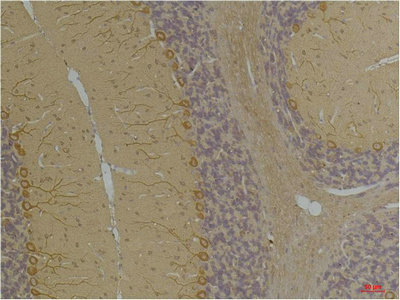

Immunohistochemical analysis of paraffin-embedded Rat BrainTissue using Kv1.8 Rabbit pAb diluted at 1:200.

Immunohistochemical analysis of paraffin-embedded Mouse BrainTissue using Kv1.8 Rabbit pAb diluted at 1:200.